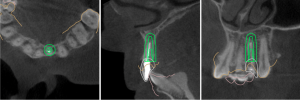

This video demonstrates immediate implant placement in the esthetic zone following atraumatic extraction of a lateral incisor. Emphasis is placed on preserving the hard and soft tissue architecture critical for predictable esthetic outcomes.

The procedure is presented step by step, including minimally traumatic extraction techniques, immediate implant placement, and fabrication and placement of a customized healing abutment to support peri-implant soft tissue contours. Clinical principles for maintaining papillae, controlling the emergence profile, and optimizing soft tissue healing are highlighted.

- Indications and case selection for immediate implants in the esthetic zone